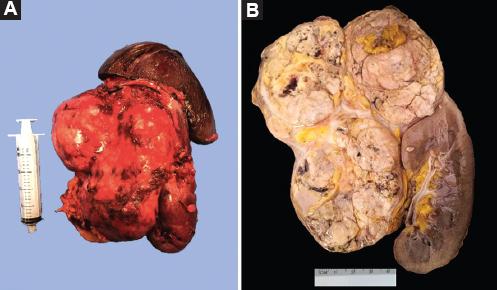

Varón de 43 años con diabetes mellitus tipo 2 en adecuado control. Inició con dolor de tipo cólico en el hipocondrio izquierdo, que se irradiaba a la región lumbar homolateral, con una puntuación en la escala visual análoga de 8/10, fiebre intermitente y pérdida de peso no intencionada de 10 kg en 3 meses. La tomografía de abdomen contrastada evidenció un tumor dependiente de la glándula suprarrenal izquierda, de 10 × 12 cm, de 91 unidades Hounsfield (UH) y realce a 167 UH tras la aplicación de medio de contraste, que desplazaba las estructuras adyacentes, así como lesiones hepáticas en los segmentos VII y VIII con realce tras la aplicación de medio de contraste (Fig. 1). Las catecolaminas y las metanefrinas plasmáticas y urinarias fueron normales. Se realizó una adrenalectomía radical en bloque (Fig. 2), sin complicaciones transoperatorias, con un sangrado cuantificado en 1300 ml, adecuada evolución posoperatoria y egreso domiciliario al cuarto día. El reporte histopatológico fue de carcinoma corticoadrenal de alto grado, de 16 cm diámetro, con necrosis extensa (70%) que invade la cápsula, con presencia de invasión linfovascular focal, márgenes quirúrgicos libres de neoplasia, sin invasión a estructuras adyacentes, y con índice mitótico de 25 (Fig. 3). En la inmunohistoquímica, inhibina, Melan-A y Ki-67 (40%) fueron positivas; sinaptofisina, cromogranina y S100, negativas (Fig. 4). El paciente se encuentra actualmente en protocolo para inicio de terapia sistémica.

Figura 2 A: pieza quirúrgica de resección en bloque por actividad tumoral. B: apariencia macroscópica: tumor de gran tamaño, sólido y con extensas áreas de necrosis, que comprime el polo superior renal.